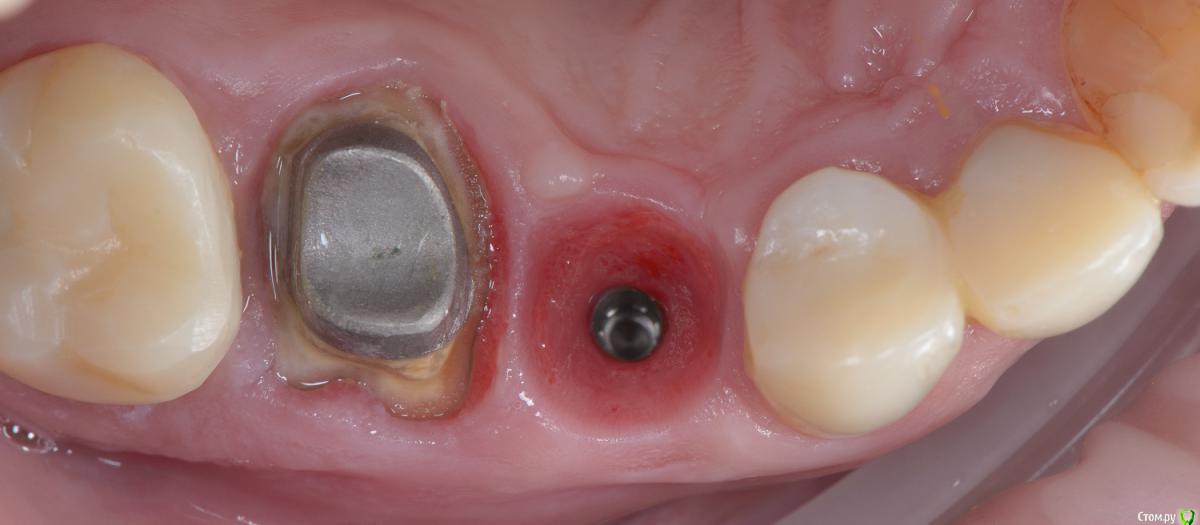

Популярный пост Mane Опубликовано 8 февраля, 2015 Популярный пост Поделиться Опубликовано 8 февраля, 2015 Зафиксировал в субботу. Собственно удалось размоделировать десну просто временной коронкой с заданным профилем прорезывания. Но для этого необходимо было выполнить ряд условий. Каких, доктора? http://i1218.photobucket.com/albums/dd412/Edikn73/emergence%20profile/Emergenceprofile001_zps040f2603.jpg http://i1218.photobucket.com/albums/dd412/Edikn73/emergence%20profile/Emergenceprofile002_zpsaa7acb0b.jpg http://i1218.photobucket.com/albums/dd412/Edikn73/emergence%20profile/Emergenceprofile003_zps259f0885.jpg http://i1218.photobucket.com/albums/dd412/Edikn73/emergence%20profile/Emergenceprofile004_zps6a15b901.jpg http://i1218.photobucket.com/albums/dd412/Edikn73/emergence%20profile/Emergenceprofile005_zps51a41bc2.jpg http://i1218.photobucket.com/albums/dd412/Edikn73/emergence%20profile/Emergenceprofile006_zps3c83a34d.jpg http://i1218.photobucket.com/albums/dd412/Edikn73/emergence%20profile/Emergenceprofile007_zpsba4d3d78.jpg 26 Ссылка на комментарий

Mane Опубликовано 10 февраля, 2015 Автор Поделиться Опубликовано 10 февраля, 2015 По поводу профиля прорезывание интересен Ваш протокол. Менялся ли ФДМ на более широкий, делались ли насечки на десне во время фиксации времяхи? Во первых - это заглубление платформы импланта - от будущего зенита до платформы - 3,5 мм . если этого не сделать - ничего не полуитсяпосле тонкого фдм зафиксировал временную коронку с небольшим надрезом по контактам. отдыхала с времянкой 1,5 мес.далее вы видели 1 Ссылка на комментарий